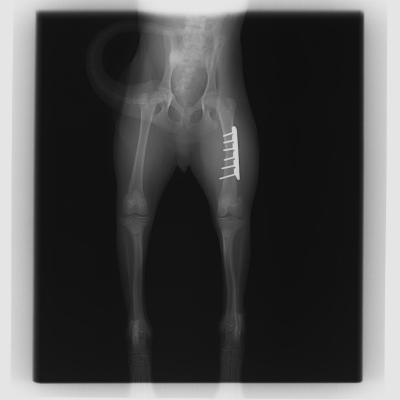

次に紹介する写真は、落下して起きてしまった大腿骨(ふとももの骨)の骨折です。

こちらも骨折用の金属プレートを用いて手術を行いました。